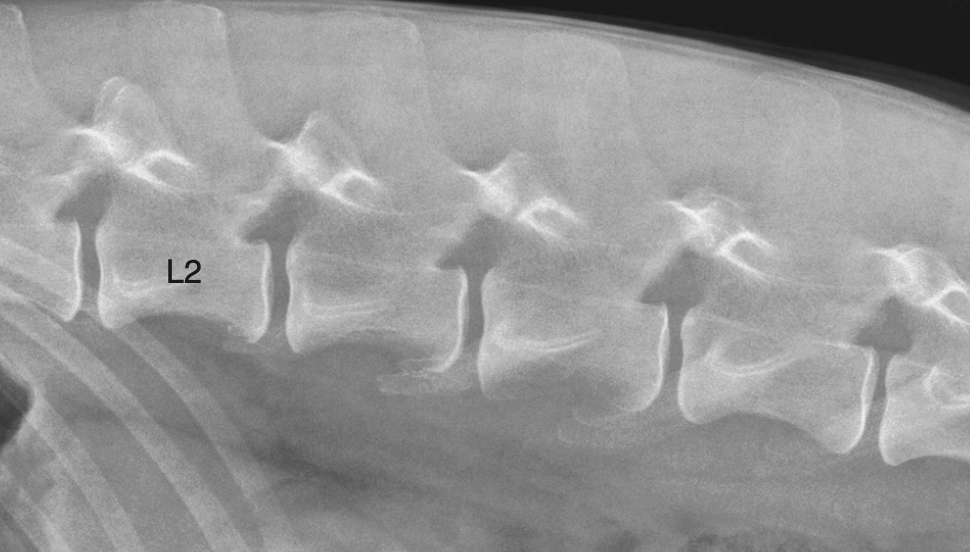

The pars lumbalis of the diaphragm attaches to which vertebrae in dogs?

A) T10 and T11

B) L2 and L5

C) L3 and L4

D) L5 and L6

A

The right and left crura of the pars lumbalis attach to the cranial ventral border of L4 and the body of L3.

Where do the crura of pars lumbalis attach?

L3 body / L4 cranioventral border

Q

Which part of the diaphragm attaches to L3/L4?

Pars lumbalis crura

2) Which of these statements is false about the pars lumbalis a) It attaches to the cranioventral border of L4 b) It is the part of the diaphragm that makes up the right and left crura c) The Attachment area on the vertebrae can appear indistinct and be mistaken for bone lysis d) It attaches to the body of L2 and 3

2) D only to l3 and l4